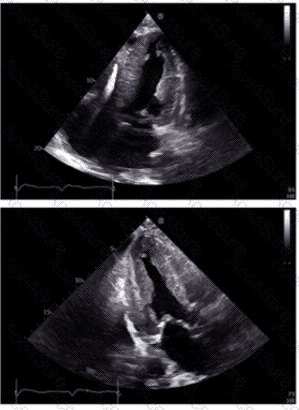

The 2D echocardiographic images show apical ballooning, a hallmark of Takotsubo cardiomyopathy, where the apex is akinetic or dyskinetic and the basal segments contract normally or hypercontract. Doppler images show findings consistent with impaired ventricular function.